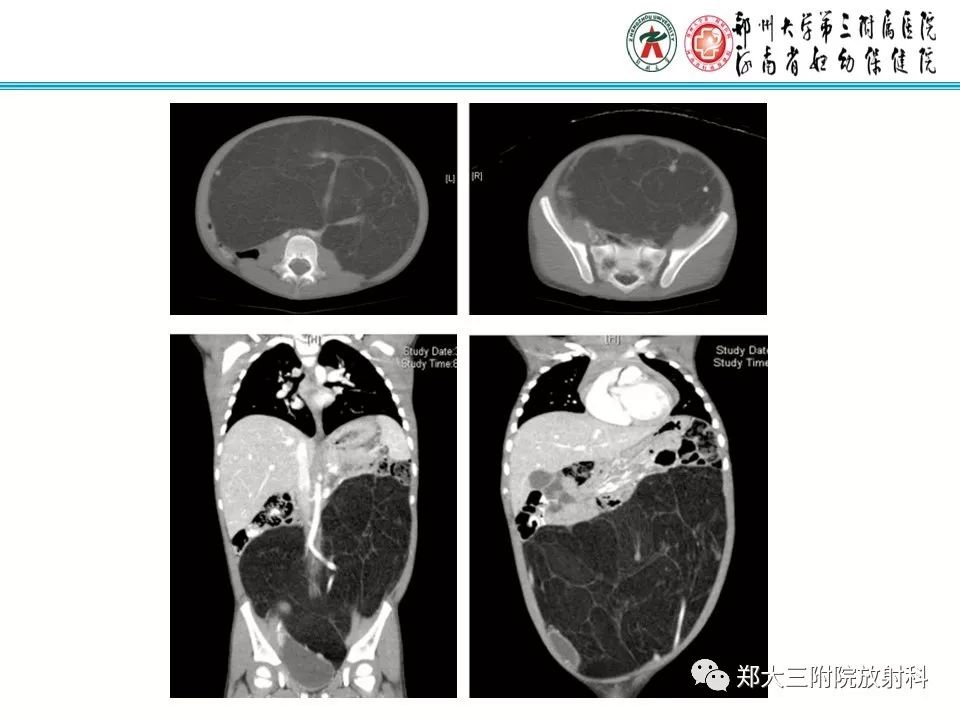

儿童颈部脂肪母细胞瘤1例CT影像诊断

【病例】儿童颈部脂肪母细胞瘤影像诊断